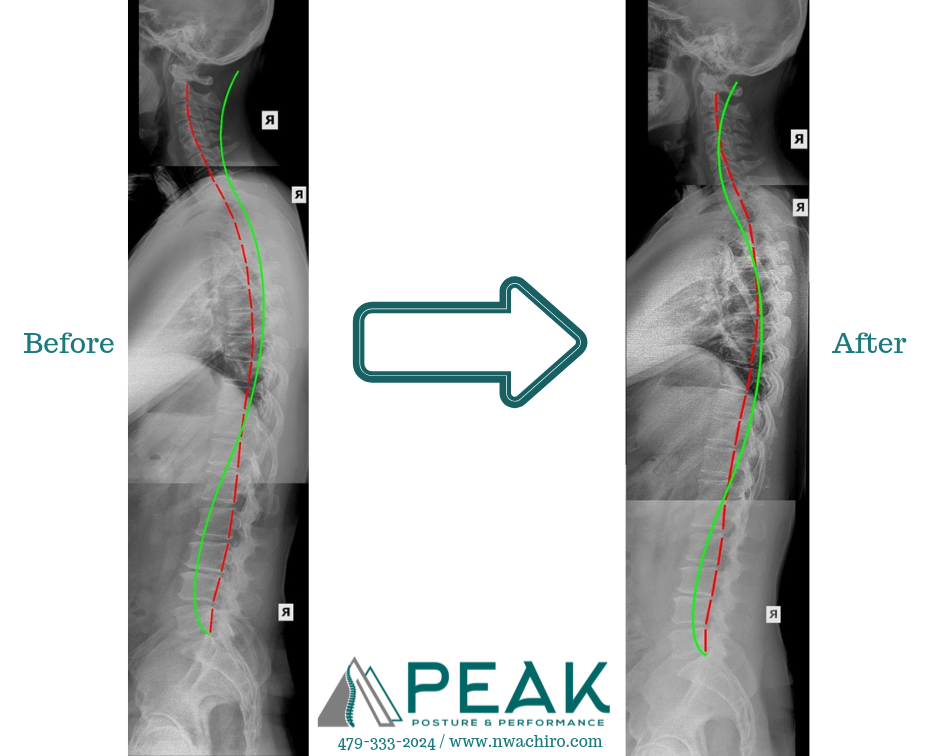

We use a mix of specialized equipment including denneroll tables with arms, neck remodeling units, decompression tables, adjustment table with drops and more. This equipment is designed to change ligaments and disc's that have had abnormal loading or mechanics for years, with out surgery and completely individualized.The exercise equipment is even more vast allowing us to strengthen the muscles for stability, increase circulation, and build better balance and movement. You can really work your key areas and see results.